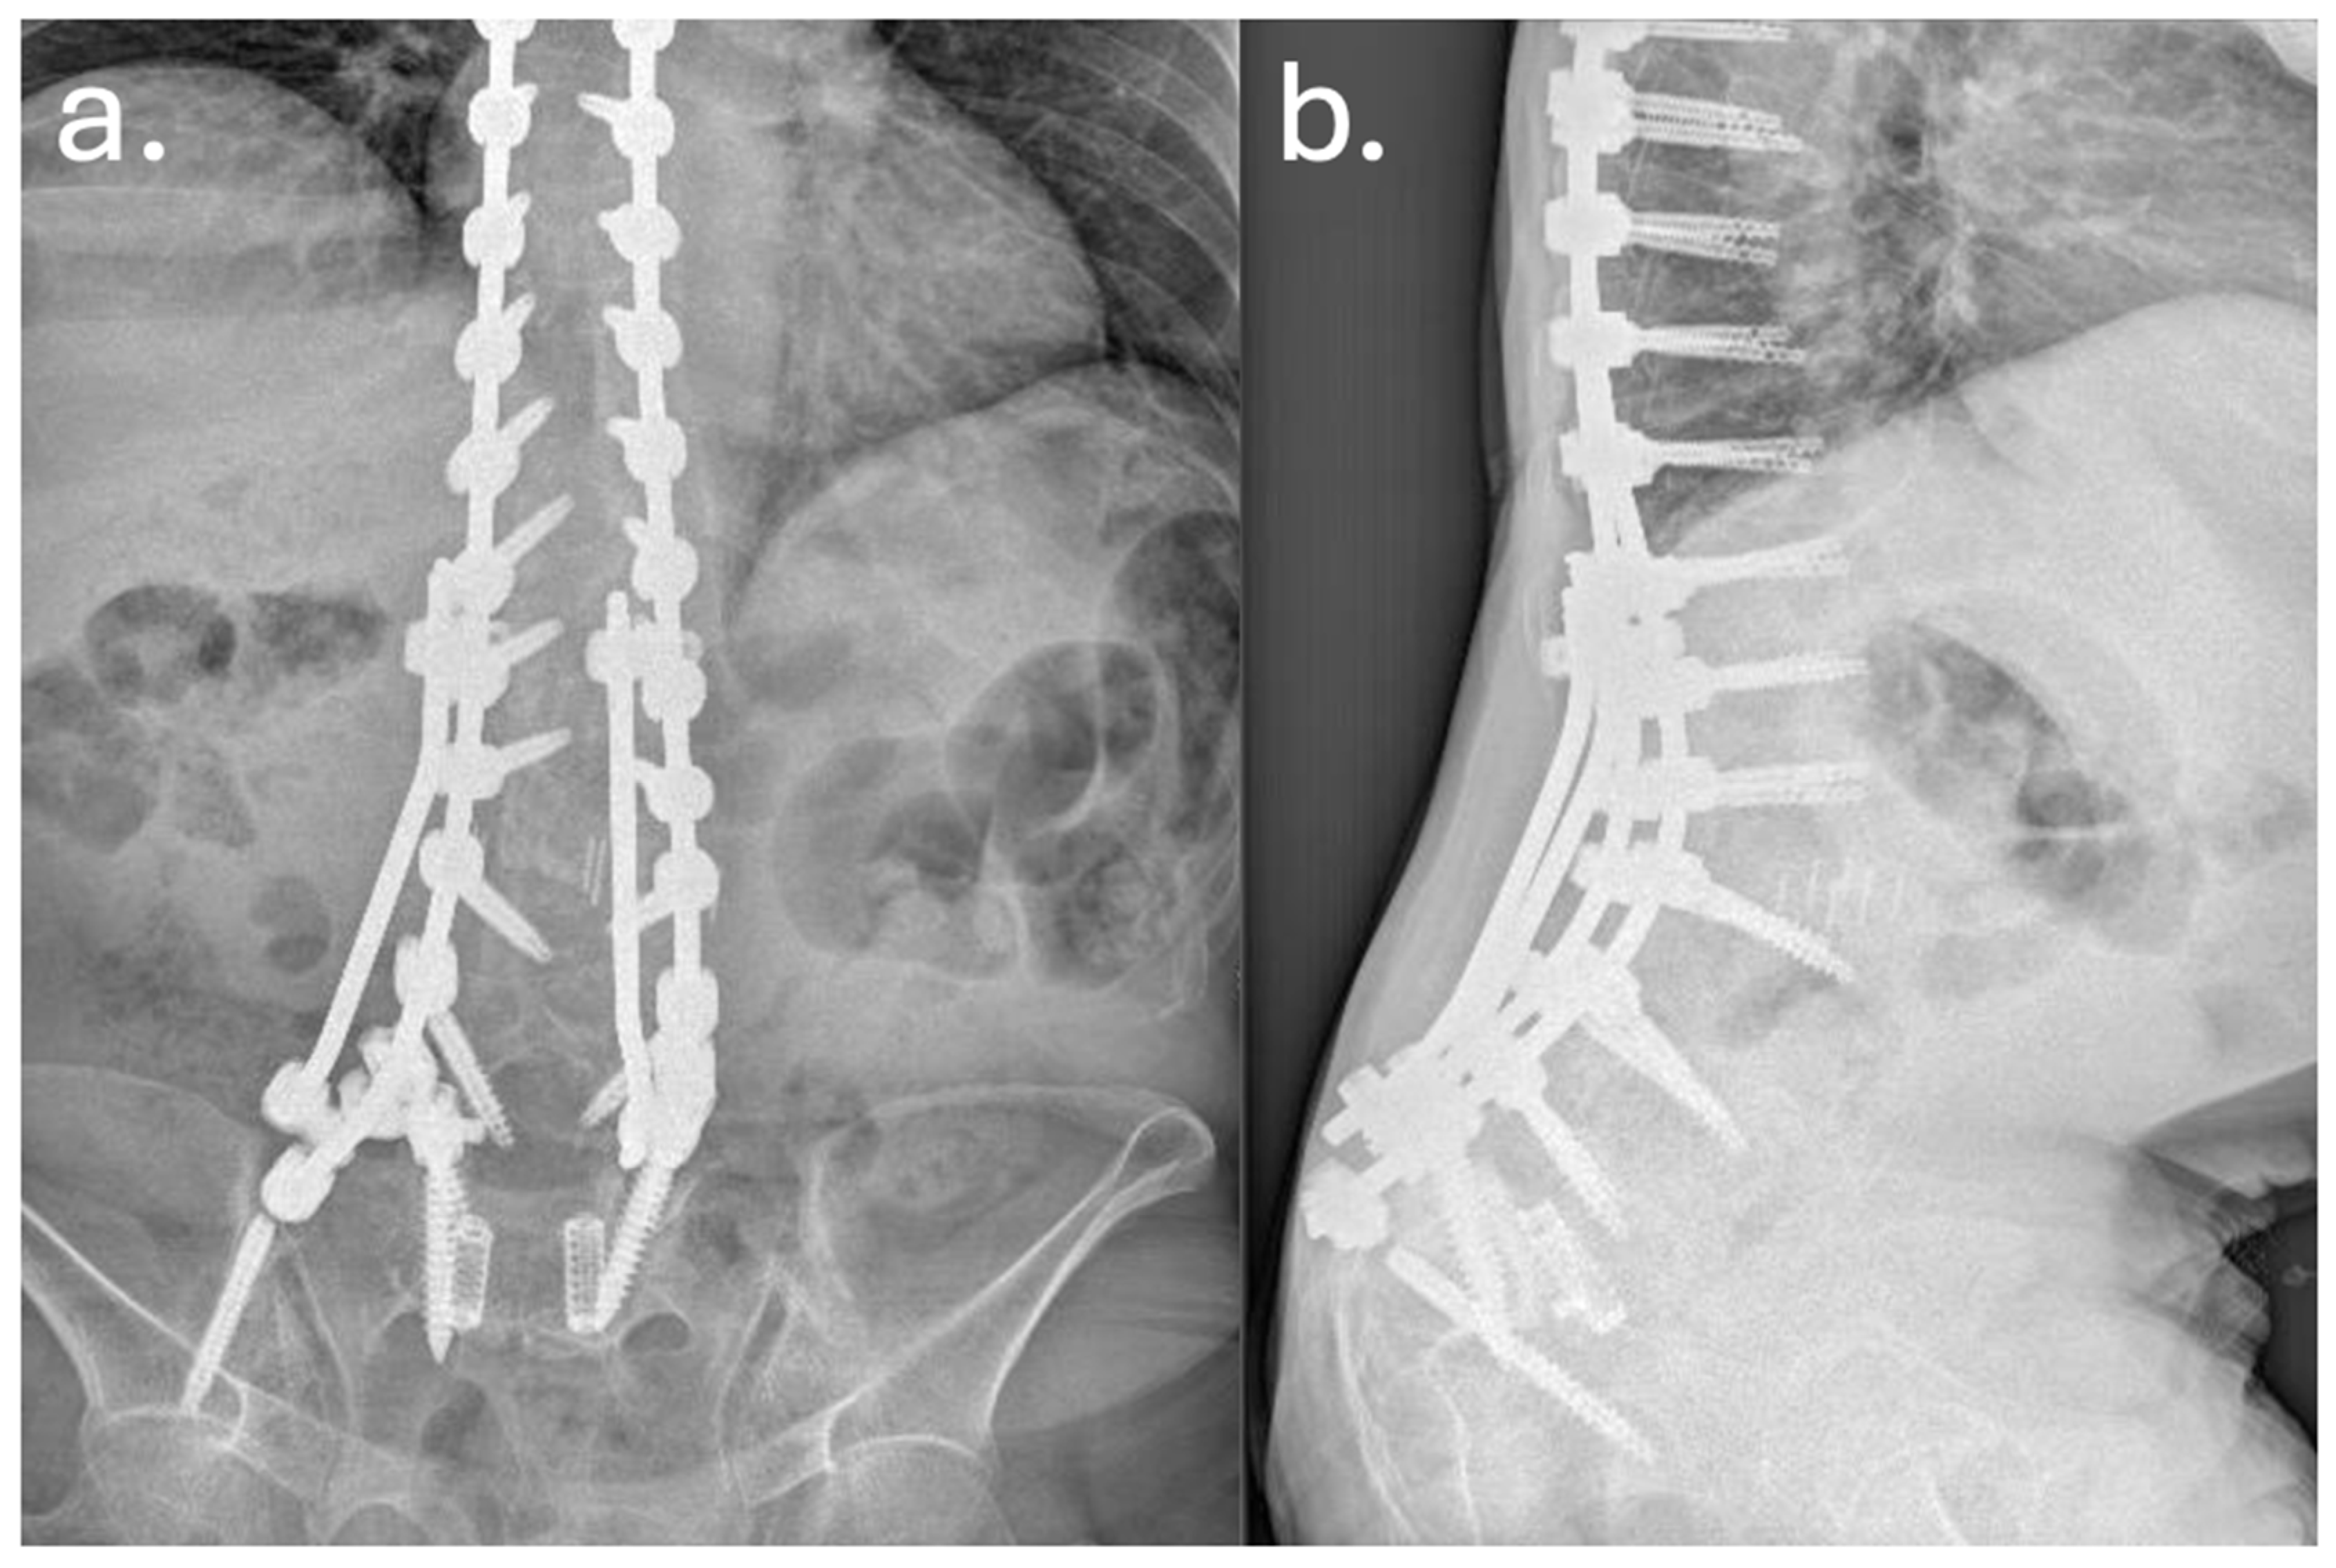

Despite temporary clinical improvement, progressive sagittal imbalance and worsening pain prompted a fourth surgery in June 2016, she underwent a major posterior revision: all prior instrumentation was removed and replaced with new rods and screws extending from T7 to the pelvis, including bilateral iliac fixation as showed in Figure 2 and Figure 3. Postoperatively, the patient developed high-grade fever and was diagnosed with a urinary tract infection due to Acinetobacter baumannii XDR. She was treated with multiple antibiotic courses, including teicoplanin, tigecycline, and colistin.

Figure 2. Preoperative (a) and postoperative (b) lateral radiographs documenting the first revision surgery with extension of the arthrodesis from T2 to the ilium. The images show restoration of sagittal alignment, with correction of the sagittal vertical axis (SVA) and improvement of lumbar lordosis.